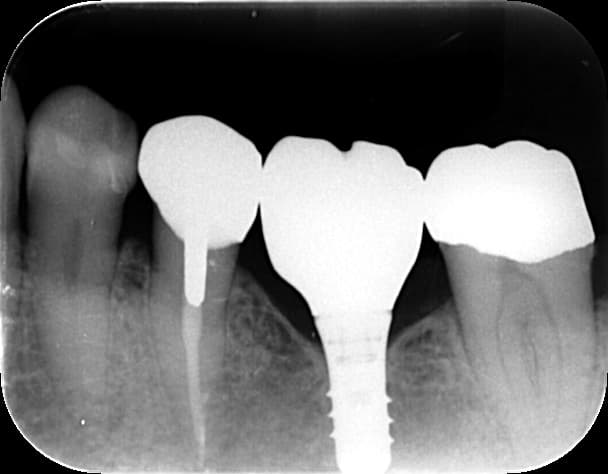

・インプラントによる負担軽減: 何度もブリッジが外れる場合、土台の歯が悲鳴を上げている証拠です。1本だけインプラントを入れることで、残っている自分の歯を削らず、負担を肩代わりさせることができます。これが結果として、他の歯を守る「最高の予防」になります。

A2. 最大のメリットは「両隣の歯を守れること」です。ブリッジは欠損部分の力を両隣の歯が1.5倍ずつ負担しますが、インプラントはその場所だけで自立します。これにより、周囲の健康な歯が過労でダメになる連鎖を止めることができます。